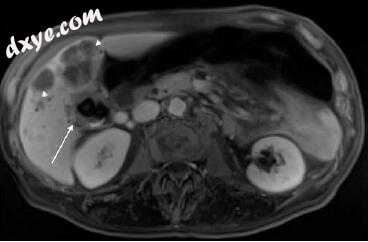

图5.4 73岁女性患者右侧半肝切除伴肝 - 空肠吻合术后复发胆管癌(箭头),平衡期相对强化MR成像